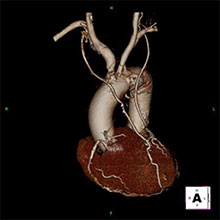

冠動脈バイパス術後3次元CT

冠動脈バイパス術後3次元CT